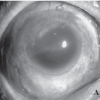

Jona MB Sy-Ongkeko, MD Archimedes LD Agahan, MD Juan S Lopez, MD Jacinto U Dy-Liacco, MD Department of Ophthalmology and Visual Sciences, College of Medicine, University of the Philippines-Philippine General Hospital, Manila, Philippines Sympathetic ophthalmia (SO) is a rare, bilateral, nonnecrotising granulomatous panuveitis that may develop after exposure of intraocular contents to the immune system, i.e., trauma, followed by a latent period and the appearance of uveitis in both the injured and non-injured eye. Both eyes are affected, with the injured eye usually presenting with uveitis before, and more severe than the uninjured eye. Its occurrence is much more likely » » » [Read more]